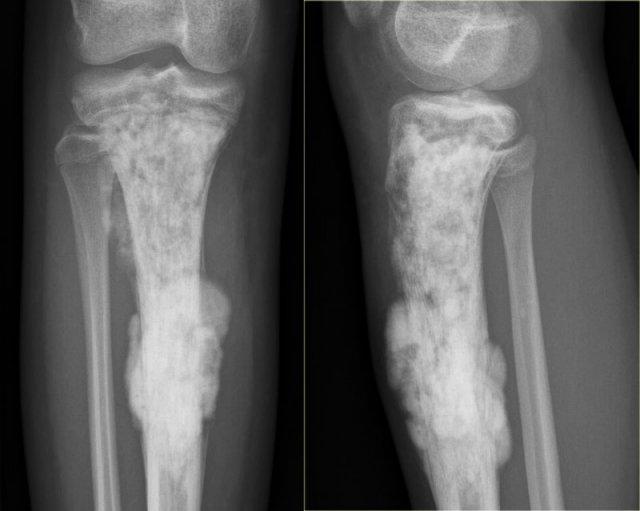

Hình ảnh cho thấy một tổn thương vôi hóa ở đầu gần xương chày mà không có đặc điểm đáng ngờ.

Đây rất có thể là một u sụn nội xương (enchondroma).

Có những đặc điểm khác ủng hộ chẩn đoán sarcoma sụn độ thấp như xạ hình xương dương tính và hình ảnh xói mòn nội màng xương trên MRI (không hiển thị).

Sarcoma sụn đã được chẩn đoán qua sinh thiết.